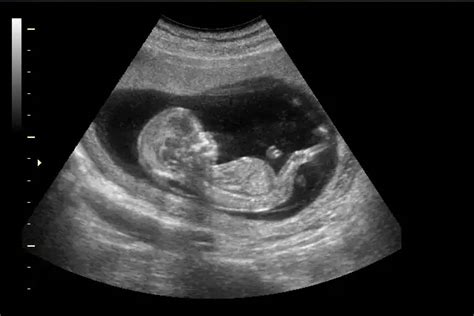

¿Cuándo debo realizarme la primera ecografía de embarazo?

Nuestro equipo de ginecólogo en Marbella recomienda realizar la primera ecografía diagnóstica entre la semana 8 y 10 de gestación.